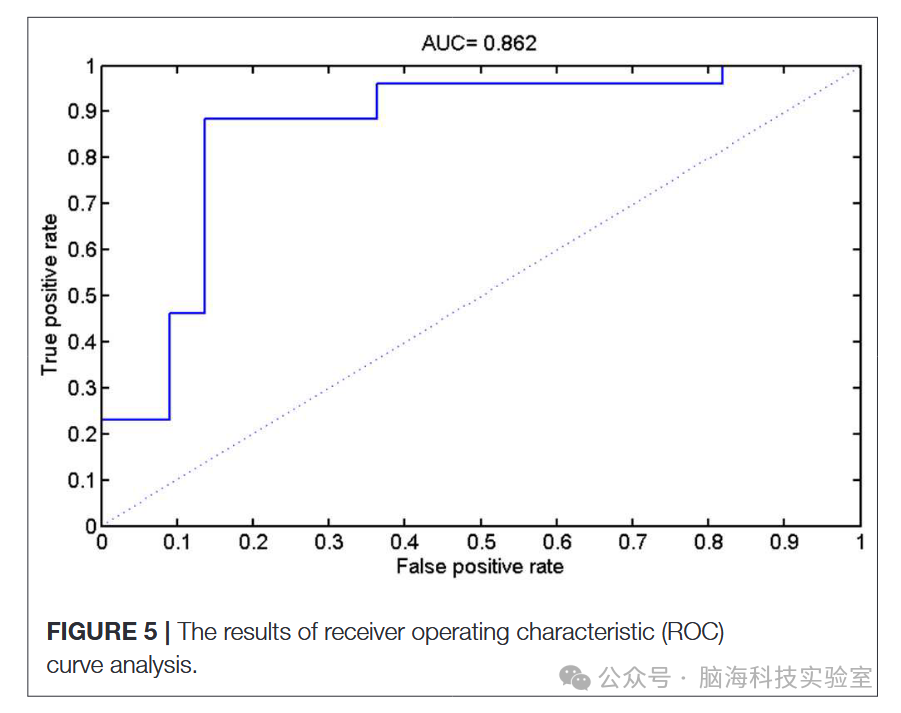

通过以每个受试者的预测函数值作为指标,研究生成了分类器的接收器工作特征(ROC)曲线(图5)。所开发方法的ROC曲线下面积(AUC)为0.862,说明分类的功效相对较强。计算Spearman相关系数以评估预测函数值和ALSFRS-R评分之间的相关性(图6)。研究观察到这些参数之间存在正相关关系(r = 0.0.397,P = 0.034)。

图5